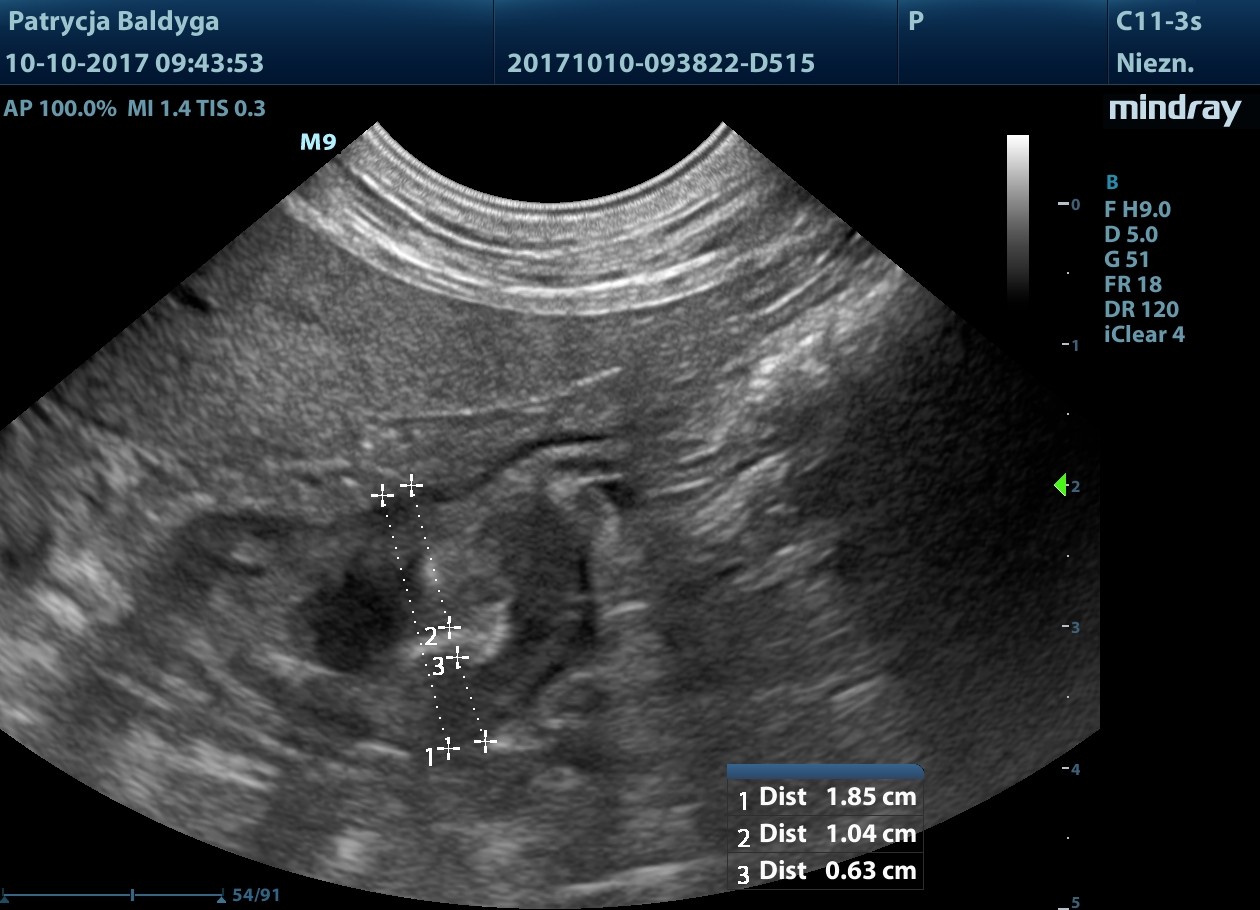

Jelito grube w przewadze w st. zapalnym, ściana o zachowanej wartwowości, pogrubiała zap. do 2,5 mm

naciekowa, śródścienna, hipoechogenna, niesymetryczna 6-18 mm, dł. 2,5 cm, warstwowość w tym miejscu zatarta, obecny okoliczny, nieznaczny odczyn zapalny (pod koniec filmu 3), ww, chłonne okrężnicze środkowe reaktywne, powiększone, hipoechogenne, zokrąglone, śr. ok. 7-8 mm